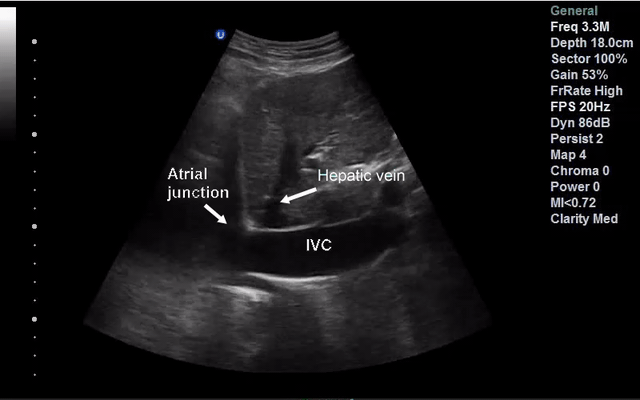

In the spontaneously breathing patient measure IVC maximal IVC diameter 2 cm distal to the right atrial junction at end expiration; in intubated patients measure at maximal inspiration. Repeat the measurement at end inspiration (or expiration in intubated patients) and calculated the collapsibility using the formula below:

- Hepatic vein drains into it

- Connects to the right atria